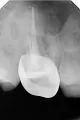

Мне прочищали каналы и клали лекарство в зуб шестерку, ставили временную пломбу. Все эти два месяца при пружинистой ходьбе в голове раздавался звук, как часы. И сейчас вкрутили штифт для культи под коронку в канал, все каналы запломбировали, а звук все равно есть.

Откровенно говоря, нет. Но штифт — неправильная конструкция, в этом случае стоит показаться более профессиональному стоматологу.

Если Вы выложите снимок, я постараюсь Вам помочь.